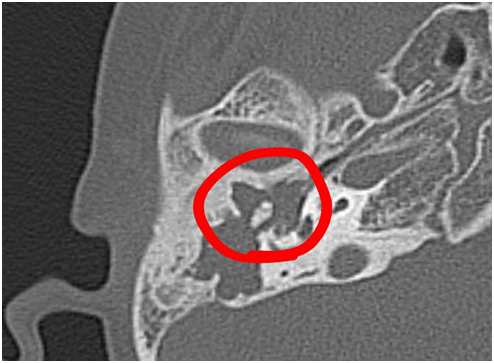

Normada və xolesteatoma olan xəstələrdə üz kanalının Köndələn kəsik sahəsinin müqayisəsi Kərimzadə Gülnarə, Mövsümov Nəriman, Panahian Vəfa